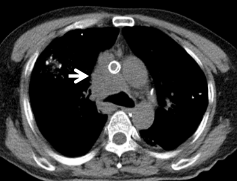

经过12次放疗,患者气短明显改善,从全程依赖无创呼吸机逐步过渡到间断使用;完成17次放疗后,患者仅需高流量鼻导管吸氧,胸闷气短大幅缓解,影像学显示肿瘤病灶显著缩小。令人欣喜的是,患者从完全无法平卧,现已基本能平躺休息,生活质量得到极大提升。

放疗前